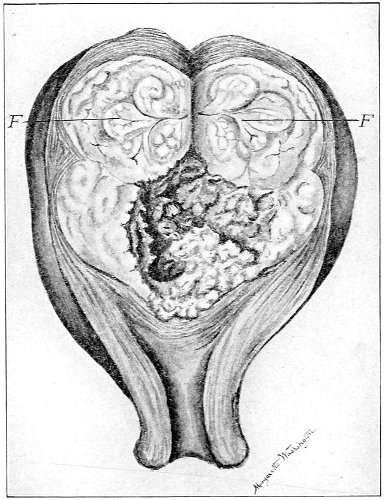

The symptoms of this condition are due to retention of the uterine discharges. There is no discharge of 53 menstrual blood from the vagina. Attacks of pain occur periodically at the menstrual periods. A cystic tumor, which may be felt by rectal examination, is present. The tumor consists of the distended portion of the vaginal canal (hematocolpos), and sometimes of the distended cervical canal and body of the uterus. The contents of the hematocolpos are usually sterile, although they may become purulent (pyocolpos).

The diagnosis is readily made by vaginal and rectal examination.

Treatment consists in incision and excision of the vaginal septum and the suture of the vaginal mucous membrane above to that below the obstruction. In very severe cases it is difficult to maintain the patulous condition of the vaginal canal on account of subsequent cicatricial contraction. In such cases the repeated passage of vaginal bougies or the transplantation of mucous membrane has been resorted to.